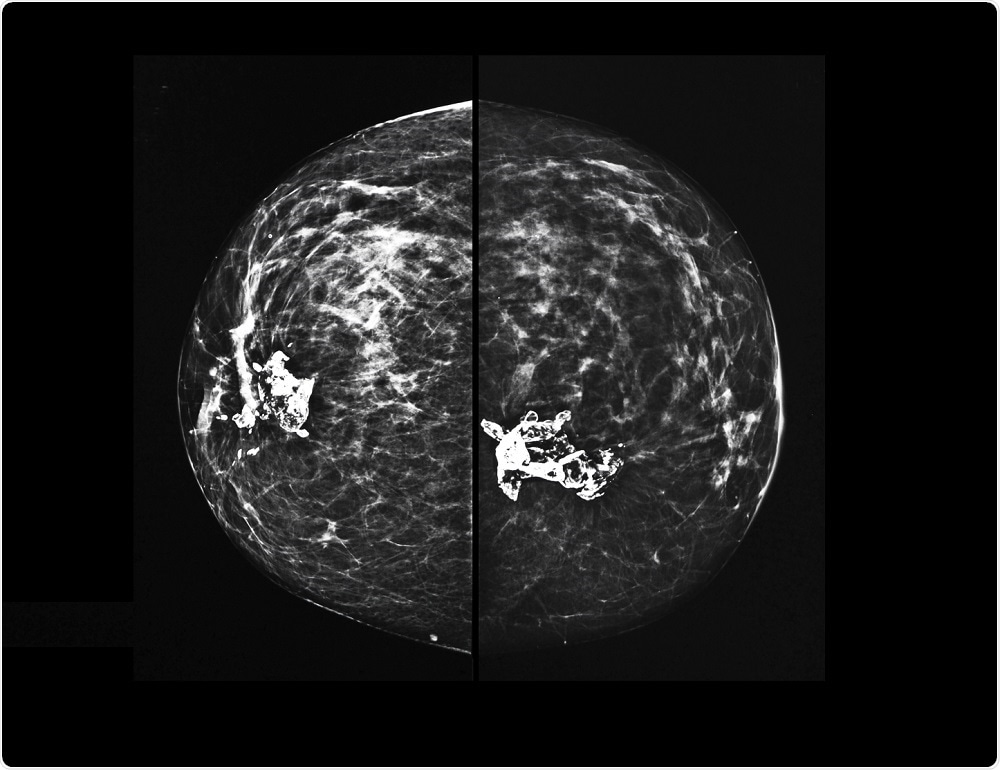

X-ray mammography of breast tissueSemnic | Shutterstock